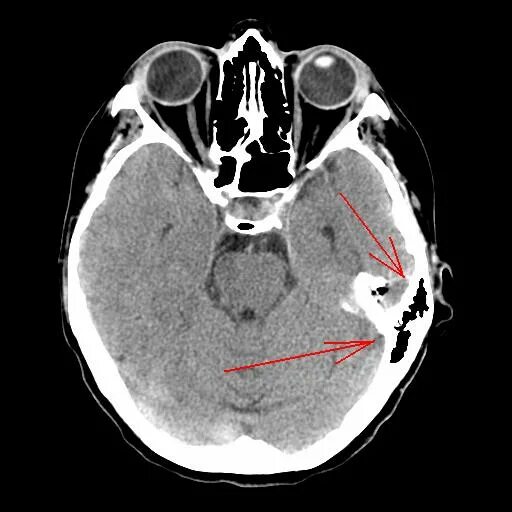

Болит кт